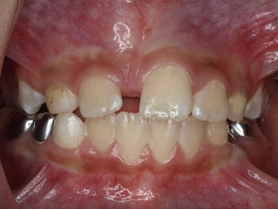

Răng thừa làm cho R21 mọc thưa và lệch về phía môi Răng thừa (a) làm R11 (b) bị kẹt không mọc ra được

Răng thừa gây nang xương hàm trên Răng thừa mọc vào tiền đình mũi

Hình 2: Một số biến chứng của răng thừa